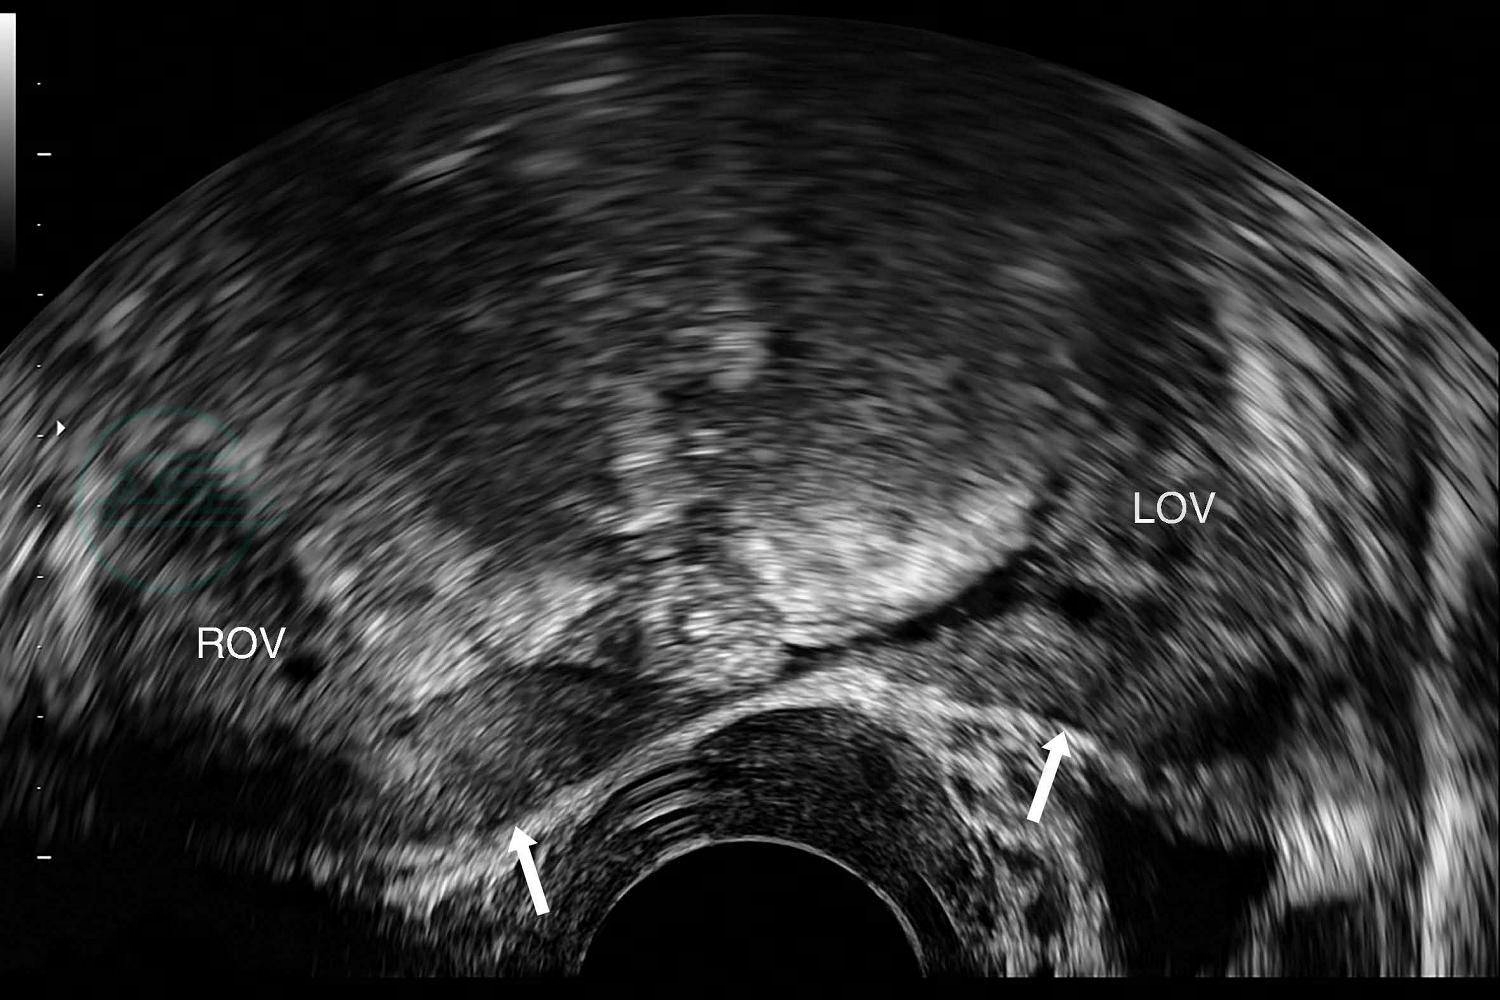

对始基子宫患者行腔内超声检查时,可在膀胱后方扫查到一等回声肌性结构(图1),宫体宫颈结构分界不清,且宫体与宫颈的比例失调,无宫腔线,或有宫腔线而无内膜回声。双侧始基子宫者,盆腔中央未见子宫声像,需在盆腔两侧仔细扫查,可在两侧卵巢旁查见两个等回声肌性结构(图2),回声均匀、边界清楚,与正常子宫肌层回声类似。

图2腔内超声双侧始基子宫二维灰阶声像图

图示盆腔内双侧卵巢(ROV、LOV)旁两个子宫样肌性回声结构(箭)